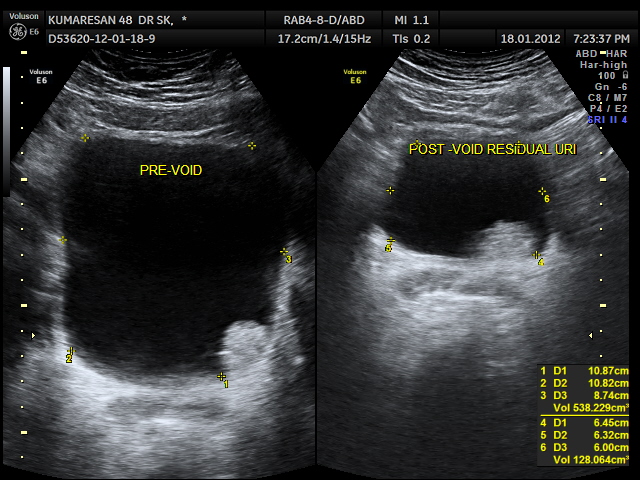

47 year old man presented with complaints of painless hematuria ; he had a similar self limiting episode 3 months ago , which he ignored.His ultrasound pictures are given below

the next is a post void picture showing the mass